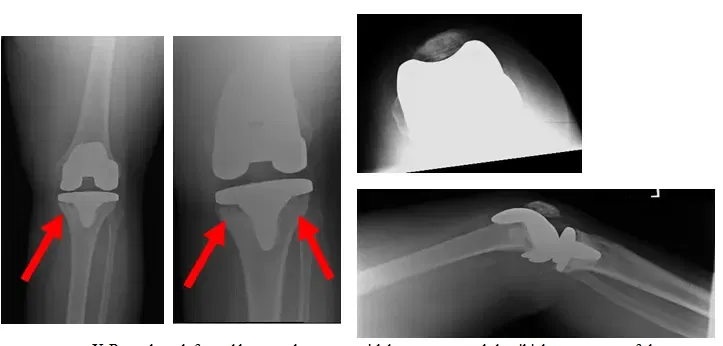

El paciente es un varón de 85 años que se presentó con una prótesis tumoral de rodilla izquierda luxada. El paciente llevaba 3 meses en el postoperatorio de una artroplastia total de rodilla (ATC ) con tumor izquierdo Reconstrucción. El paciente requirió cirugía para...

El paciente es un varón de 25 años que nos fue remitido por otro cirujano ortopédico y acudió con una fractura anterior de rótula que no estaba cicatrizando correctamente. El paciente sufría fuertes dolores y se había sometido a una intervención quirúrgica previa para...